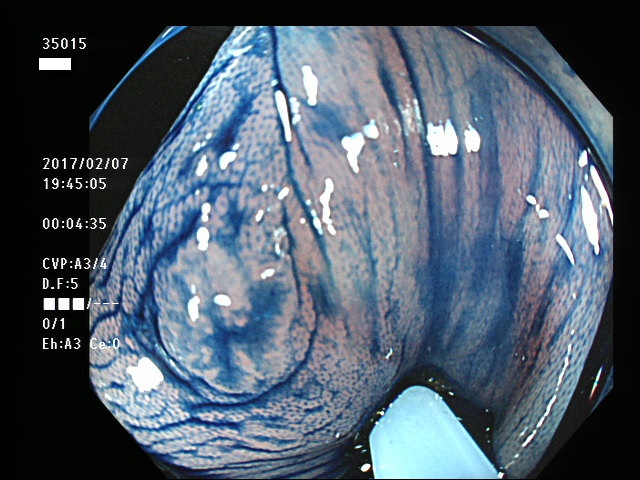

上記100名より抽出した平坦・陥凹型腺腫・SSAP(=癌化の危険が高いが見落としやすい病変)の内視鏡写真

35000 35002 35004 35005 35006 35008 35009 35010 35015 35018 35019 35021